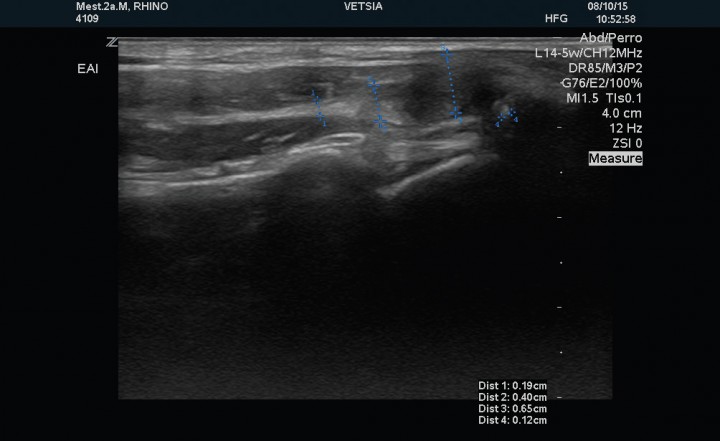

Al finalizar la segunda fase del tratamiento de rehabilitación se repitió la exploración ecográfica. Dicho examen evidenció un tendón del músculo infraespinoso de 2,3 mm de grosor, el tendón del músculo supraespinoso presentaba un grosor de 1,9 mm en su porción tendinosa, 4,0 mm en la transición fibrocartilaginosa y de 6,9 mm en el fibrocartílago, con un foco de mineralización de 1,7 mm de diámetro (Fig. 5). El tendón del músculo bíceps presentaba un grosor de 2,7 mm y la cápsula sinovial se observó de grosor normal, sin evidencia de signos de tenosinovitis (Fig. 6).

<p>Corte sagital del tendón del músculo supraespinoso izquierdo posterior al tratamiento, en el que se observa disminución de la mineralización del tendón (medida número 4).</p>

Figura 5

Corte sagital del tendón del músculo supraespinoso izquierdo posterior al tratamiento, en el que se observa disminución de la mineralización del tendón (medida número 4).